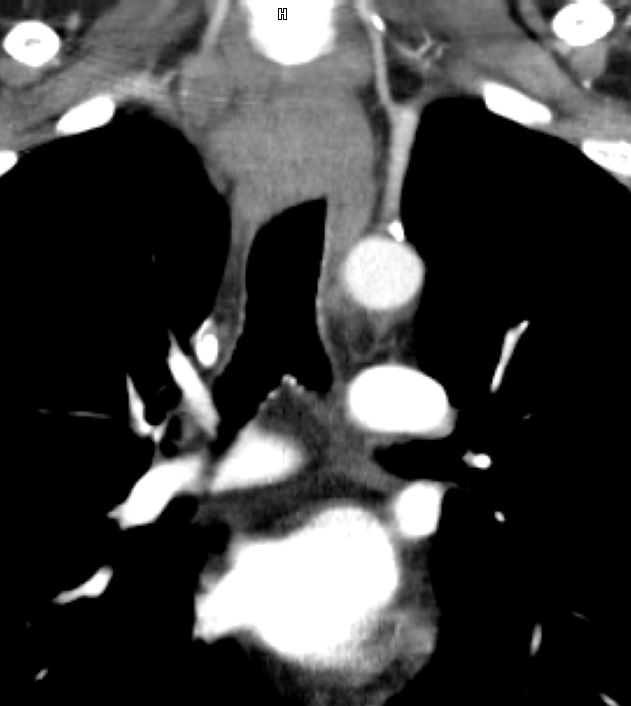

Rezidiv nach Radiochemotherapie eines kleinzelligen Tracheakarzinoms mit großer supraclavikulärer Metastase | |||